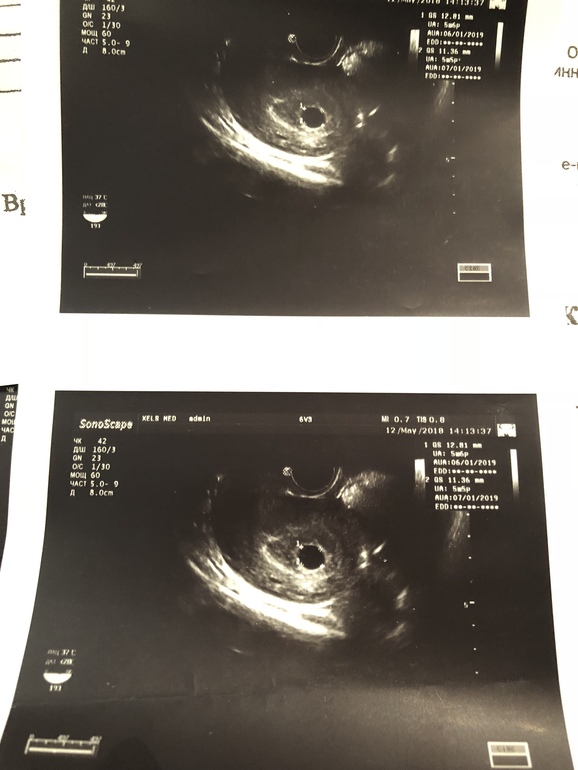

Через пару дней я вернулась в Москву и роняя кеды понеслась к своей гине. Гиня меня рассмотрела со всех сторон и постановила, что маточной беременности малого срока быть, плодное яйцо в матке - повторный контроль через 10 дней 🎉🎊🎊!!

Вроде неплохо! Через 10 дней после первого УЗИ я полетела с пачкой хгч и анализов на вторую встречу со своим внутренним жителем)

Беременность уже соответствовала 5 неделям 6 дням 😍😍. Всё было прекрасно